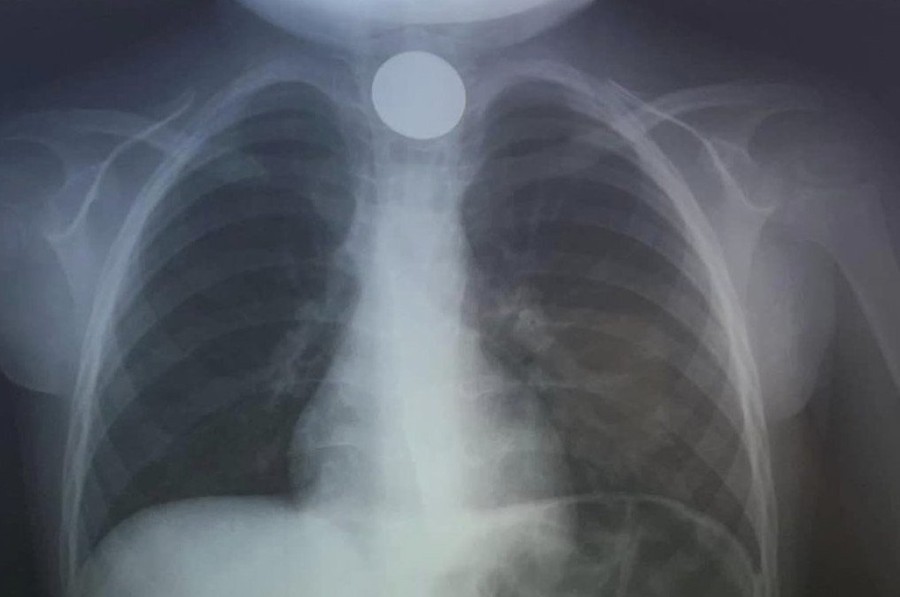

Όταν έφτασαν στο ΠΑΓΝΗ, η πρώτη κίνηση των γιατρών ήταν να του κάνουν ακτινογραφία, για να δουν σε ποιο σημείο ακριβώς είχε σταθεί το νόμισμα και αμέσως μετά προχώρησαν στη διαδικασία αφαίρεσής του. Δεν πέρασε πολύς χρόνος και οι γιατροί κατάφεραν να αντιμετωπίσουν επιτυχώς το επείγον περιστατικό, λύνοντας ταχύτατα το πρόβλημα.